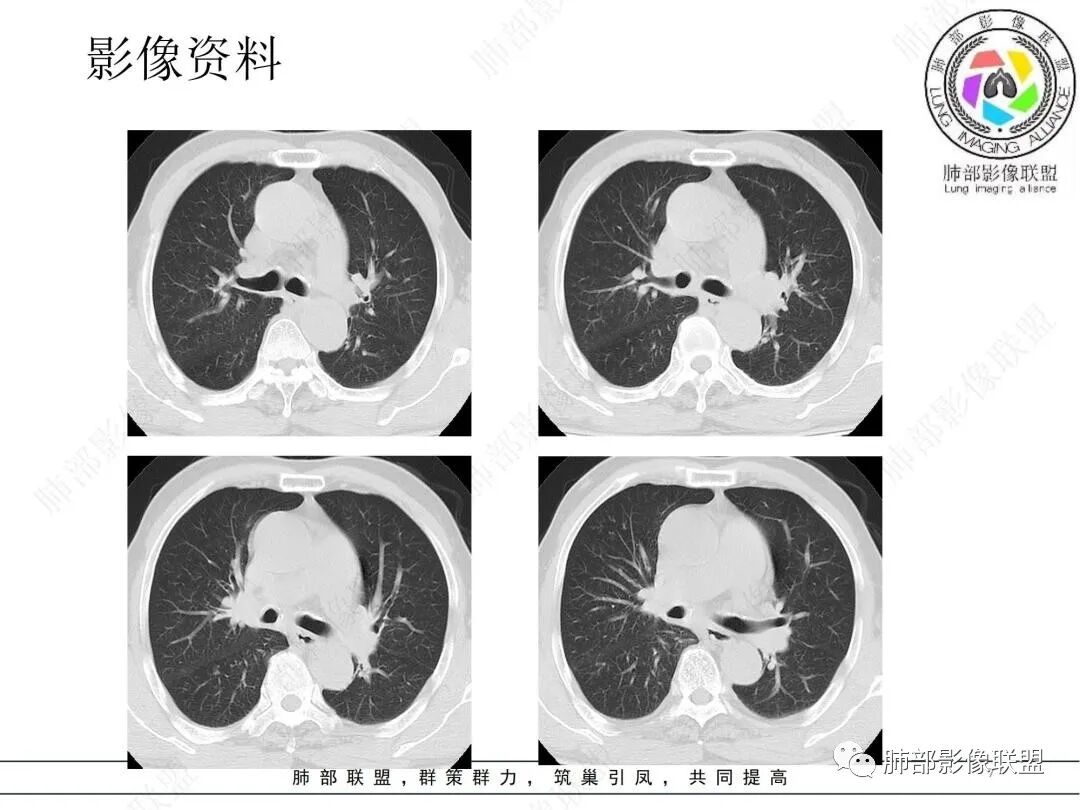

临床考虑肺结核,抗结核后3个月复查病灶明显缩小

琦遇:好病例!支气管爬行;右肺中叶有树芽征;右侧分支支气管壁弥漫性增厚了。右肺下叶内基底段支气管通而不畅。

邓文睿:这个中间还有一次复查,是部分吸收,我没放图,后面是全部吸收了。

两肺下叶背段都有病灶,可能大家忽略了。第二次复查的时候明显缩小,但是支气管还是没通,没敢除外肿瘤。第三次才全部吸收。这里放的是最后一次复查,已经完全吸收,中途还有一次复查部分吸收没放上来。

尘缘:患者炎性指标高,有支气管爬行征,支气管壁增厚,未完全堵塞,有点仙人掌的味道,而且纵隔脂肪间隙虽然模糊,但无明显肿瘤样强化。所以肯定先排查结核。所以用任何一种肿瘤都不好全部解释的,最先要排查的就是结核。

(1)病灶形态和分布:双肺散在点片影,可见树芽征。右肺下叶内基底段实性密度团块状影,底部坐落膈面、浅分叶,略呈圆锥形沿血管支气管束探及肺门,可疑“支气管爬行征”。奇食窝区分出子灶。病灶轻中度强化不均,斑片状低密度无强化区,疑坏死,未见钙化。右肺门及淋巴结肿大。

(2)支气管和血管:右肺支气管分支管壁弥漫性增厚,中间段支气管散在结节样凸起,右肺下叶内基底段支气管闭塞,但远端可疑复出。余病灶围绕支气管腔内远端无明显阻塞性不张。内部血管走形自然,提示包绕为主。

综上:病灶形态与肺段契合,血管穿行自如,更符合炎性病变,支气管腔内改变等,结核有待排除。存在支气管腔内改变,尤须支气管镜探查。

就病理而言,对存在结核不持异议,但短期内吸收太彻底,病灶主体应更多为普通炎性浸润。